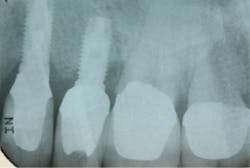

This financially expedient decision can have untoward consequences in terms of implant success. Numerous studies have shown that the composition of the microflora for both periodontitis and peri-implantitis is the same (4). In addition, other studies suggest that bacteria from a periodontally involved tooth can subgingivally colonize an implant placed in the same mouth within a two-week period of time (5). Overwhelming evidence suggests that periodontal therapy needs to be initiated prior to implant therapy in order to decrease the bacterial load that can infect dental implants and cause peri-implantitis. Other studies have shown that even in edentulous patients, periodontal pathogens can be located in reservoirs such as mucous membranes, saliva, and the pharynx. These bacteria can reinfect new dental implants placed in these patients, especially if they do not follow a proper hygiene and maintenance schedule (6). Because of these compounding variables, many studies suggest that there is an increase in biological complications associated with implants placed in patients who have untreated periodontal disease. In addition, patients with treated periodontal disease who received dental implants had a higher incidence of peri-implantitis when they were not on placed on a strict maintenance schedule when compared to those patients who were (7). For example, although the dental implant may not fail, the periodontally involved teeth next to an implant can develop problems and act as a conduit of bacteria to the adjacent implant (Figs. 2a and 2b). These bacteria can contaminate the dental implant and cause it to fail. In addition, common sense would also tell us that many of our patients have lost their teeth due to neglect and/or improper home care. Implants, although resistant to caries, are not immune to peri-implantitis or failure due to the same neglectful habits.